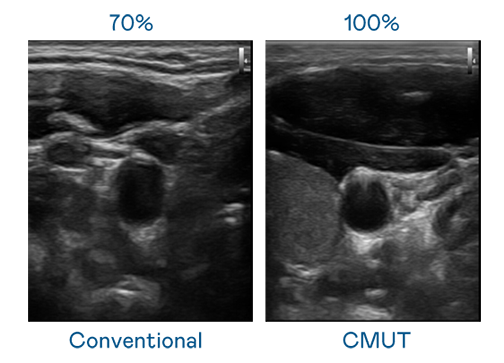

CMUT 技术是一种用电容式微机电元件来产生超音波讯号的技术。与传统 PZT 压电式技术相比,CMUT 频宽增加 30%,更宽频的超音波讯号让影像解析度大幅提升,是实现高影像品质医疗超音波扫描、促进精准医疗发展的关键技术。

大频宽带来超清晰影像

超音波影像的解析度高低,首先取决于探头能发出的讯号频宽。AG尊龙凯时 CMUT 可提供高清晰的超音波讯号,提供高频宽、高灵敏度、影像纹理细节更高的超音波影像,协助医护人员缩短影像判读时间及利用精准的医疗影像进行诊断。